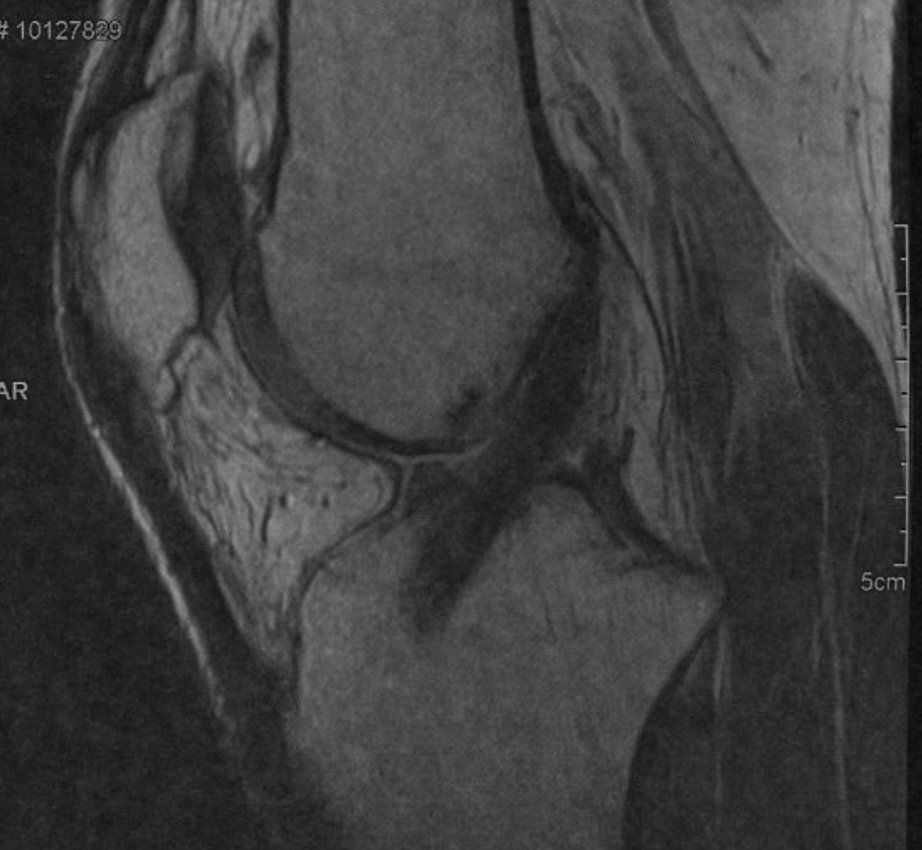

Les interventions couramment réalisées sont les arthroscopies de genou, les ligamentoplasties du ligament croisé antérieur, les ablations de matériel simples.